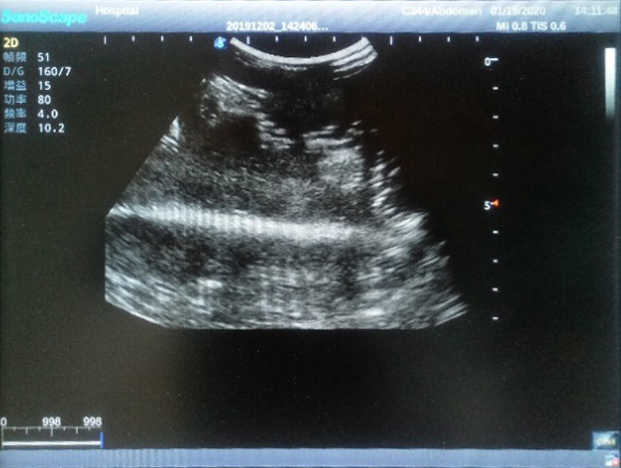

Product size(mm) 908×228×150

2)  Each model contains 8 space-occupying lesions of varying sizes, different in touch, elasticity and ultrasonogram

4) Biomimetic material allowing users to see clear and real normal tissues and space-occupying lesions that are hyperechoic, hypoechoic and isoechoic as they would see in the clinical environment